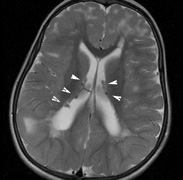

Fig. 15. Tuberous Sclerosis Complex. (a) Patient 1: Axial CT scans demonstrating typical calcification of subependymal nodules in a 13-year-old girl with a history of seizures. (b and c) Patient 2. (b) Axial T2-weighted images demonstrate calcified subependymal nodules (arrowheads) and cortical tubers typical of tuberous sclerosis. (c) Widespread cortical tubers are seen on a coronal FLAIR sequence as thickening of the cortex and high signal of the subcortical white matter.